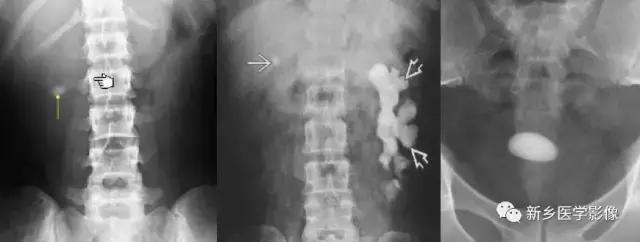

12、钙化的肠系膜淋巴结

主要表现为腹腔内弥漫性的小的、多发的钙化,大小可不一致。